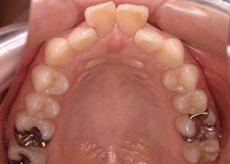

R.Y様 裏側矯正

30代 女性 会社員

症例: 施術前・施術後

| 気になっている所 | 前歯が出ている所。 |

| 装置 | 上顎 裏側矯正 下顎 デイモンシステムクリア |

| 治療方法 | 上下左右の小臼歯 合計4本抜歯。 |

| 治療前の状態 | 全体的にでこぼこと、特に上顎の前歯の前突感が強い。 |

| 治療 | 親知らずの抜歯と、歯と歯の間を少し削る事で治療上は問題のない範囲でしたが、前歯をできるだけ引っ込めたいとの希望があったため、抜歯での治療となりました。 その際、犬歯の一つ奥の第一小臼歯を抜歯する事が多いのですが、右下はそのもう一つ奥の第二小臼歯が虫歯の治療で金属が入っていたため、あえてその歯を抜歯して治療しました。 |

| 結果 | 全体のデコボコの解消と、前歯を十分に奥に引っ込める事ができました。 |